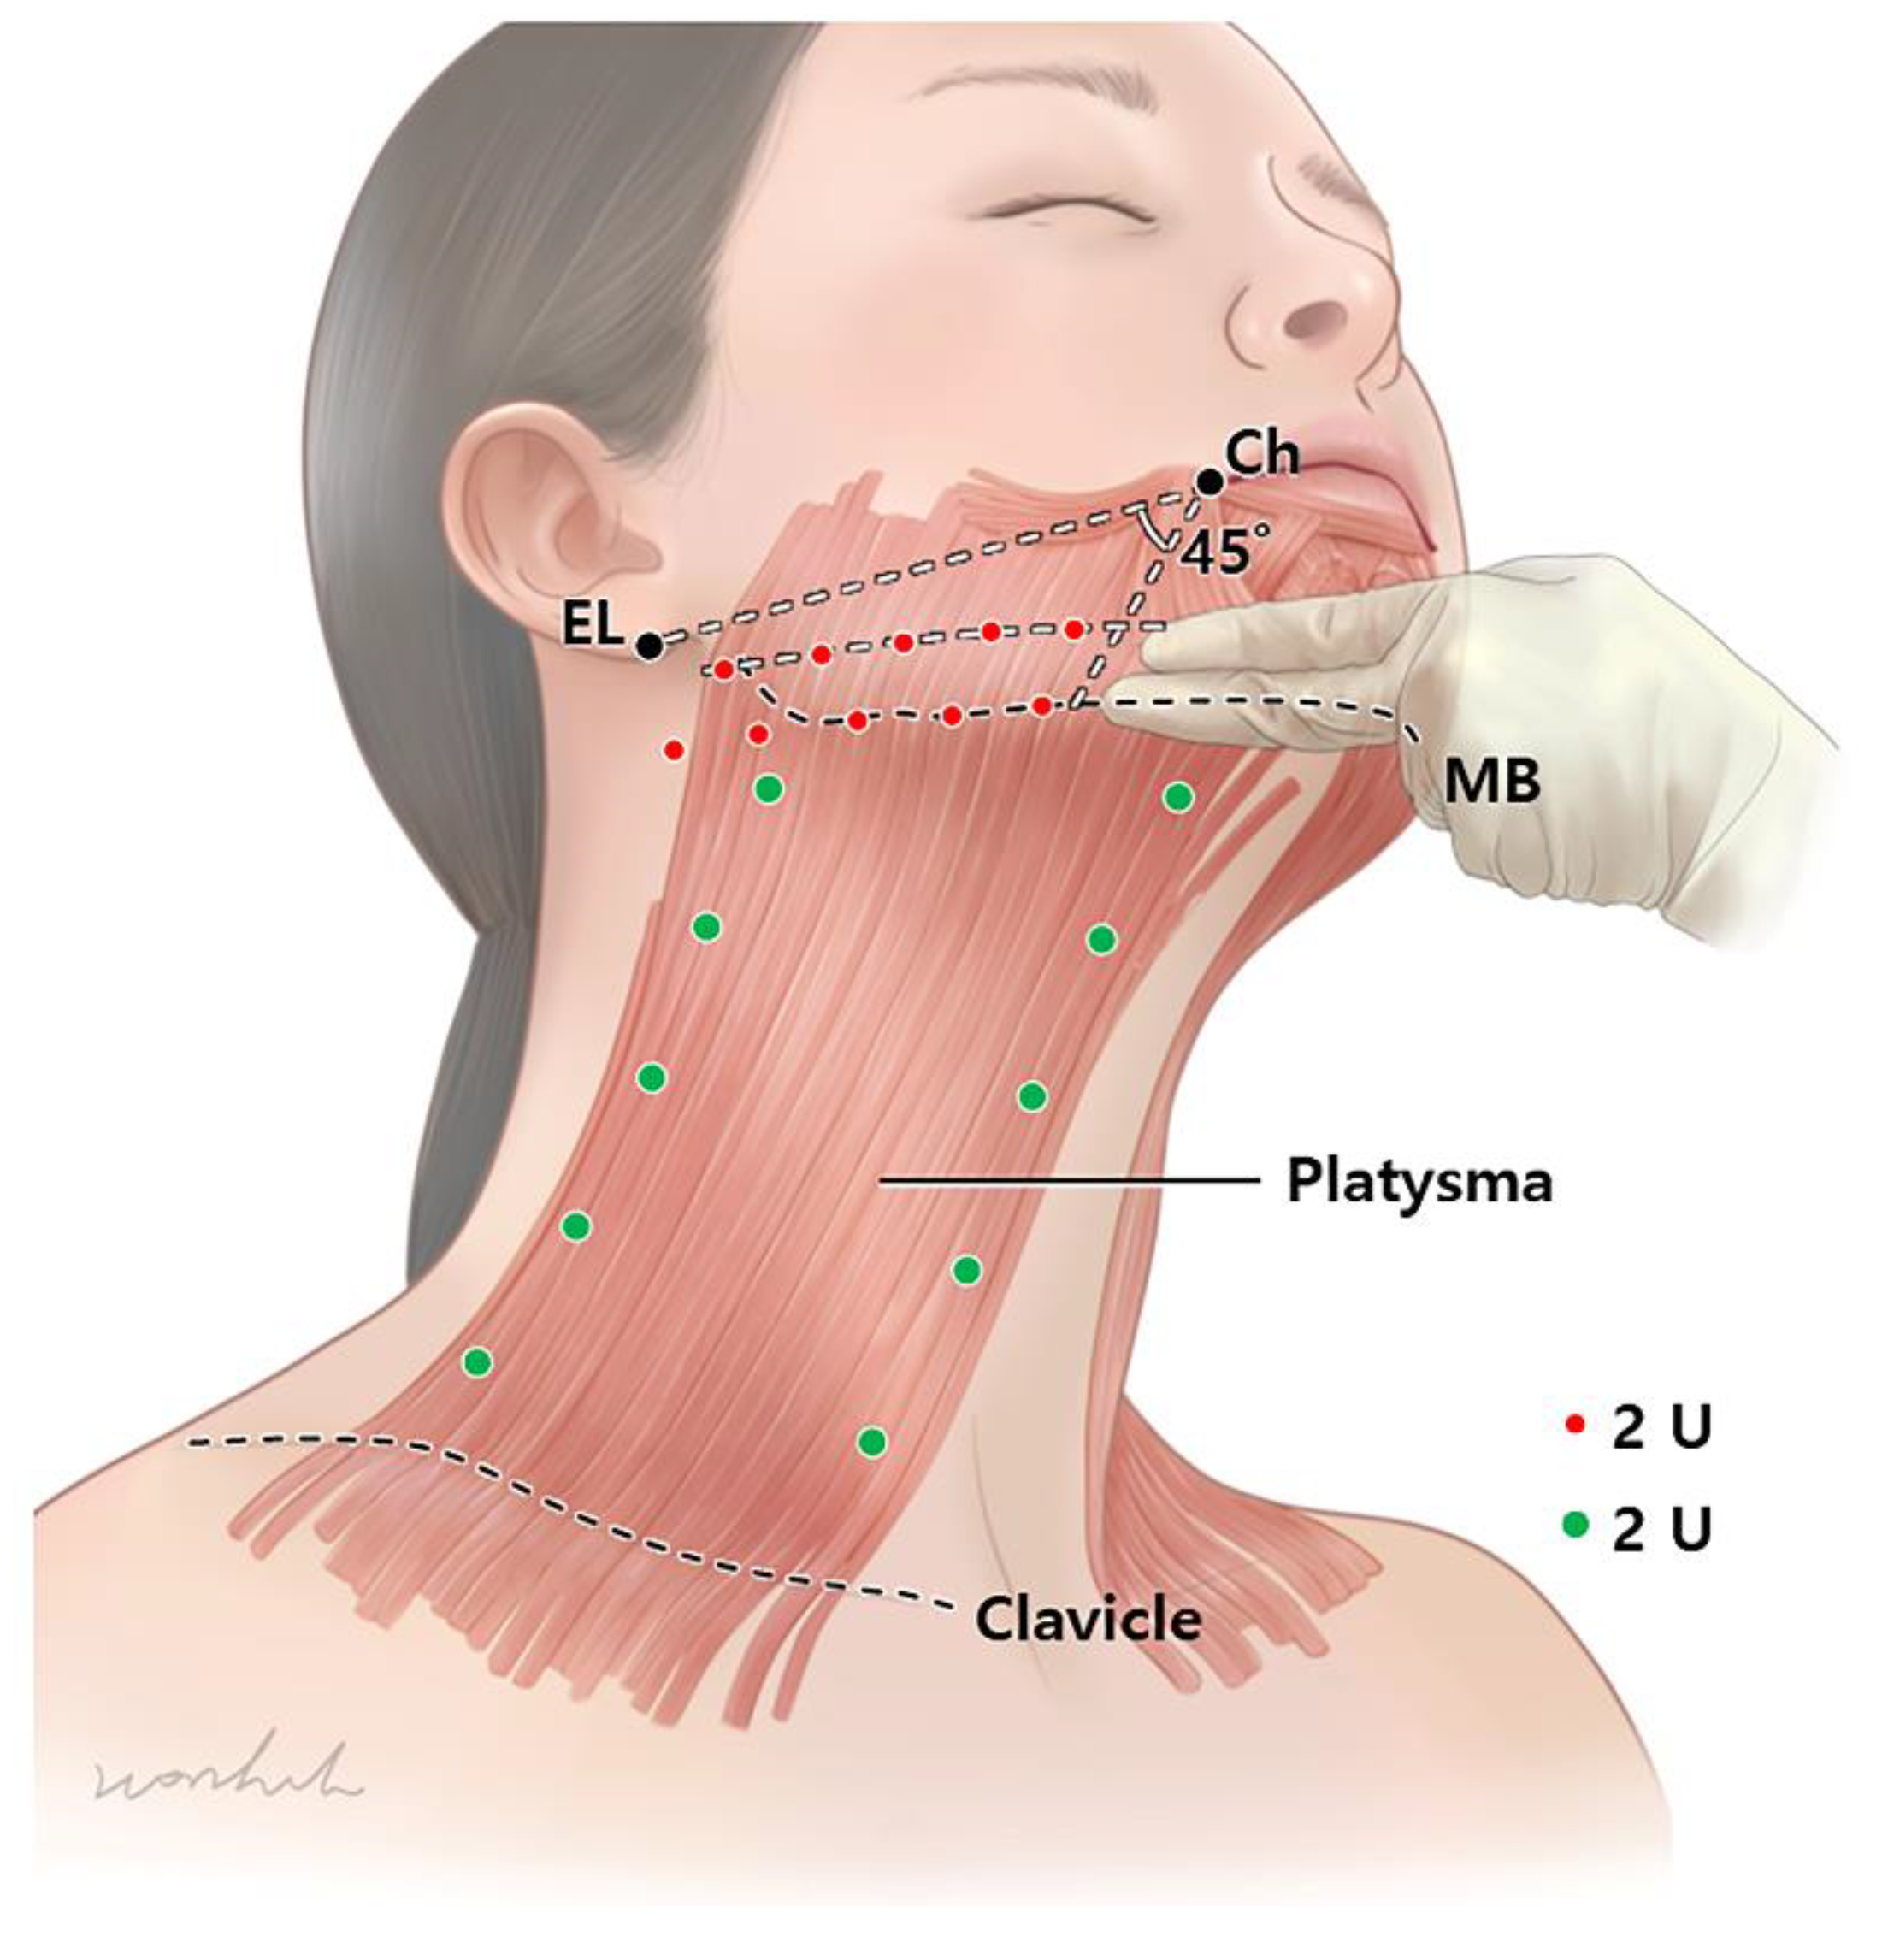

Toxins Free Full Text Anatomical Proposal For Botulinum Neurotoxin